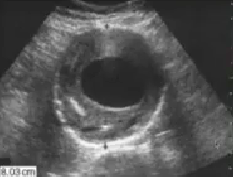

What pathology is seen here?

Aneurysm with thrombus